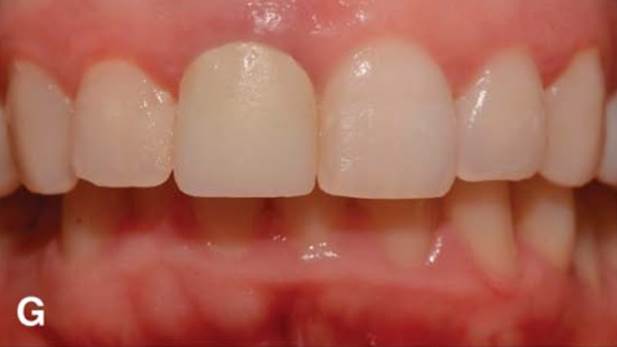

“Immediate loading of single AnyRidge implants

is a highly successful treatment modality. ”

Clinical case: Immediate post-extraction insertion of implant & immediate loading

- Courtesy of Prof. Giuseppe Luongo, Italy -

AnyRidge, immediate loading, single implant, multicenter study, maxillary anterior, Prof. Giuseppe Luongo, single replacement

AnyRidge implant system

Immediate functional loading of single implants: a multicenter study with 4 years of follow-up

/J Dent Res Dent Clin Dent Prospect 2018; 12(1):26-37 | doi: 10.15171/joddd.2018.005

https://www.ncbi.nlm.nih.gov/pubmed/29732018